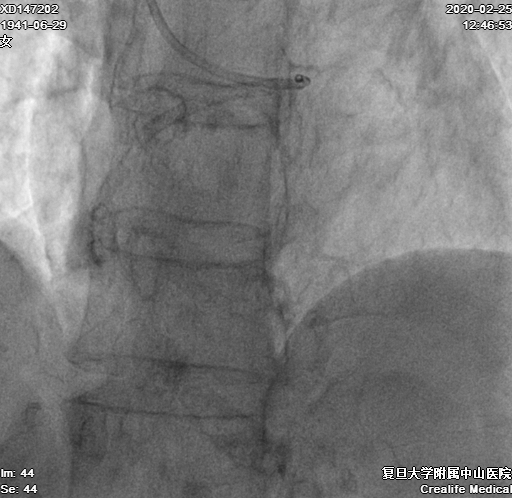

换用4F Transporta GE成功送至右冠中段(图7)

图7